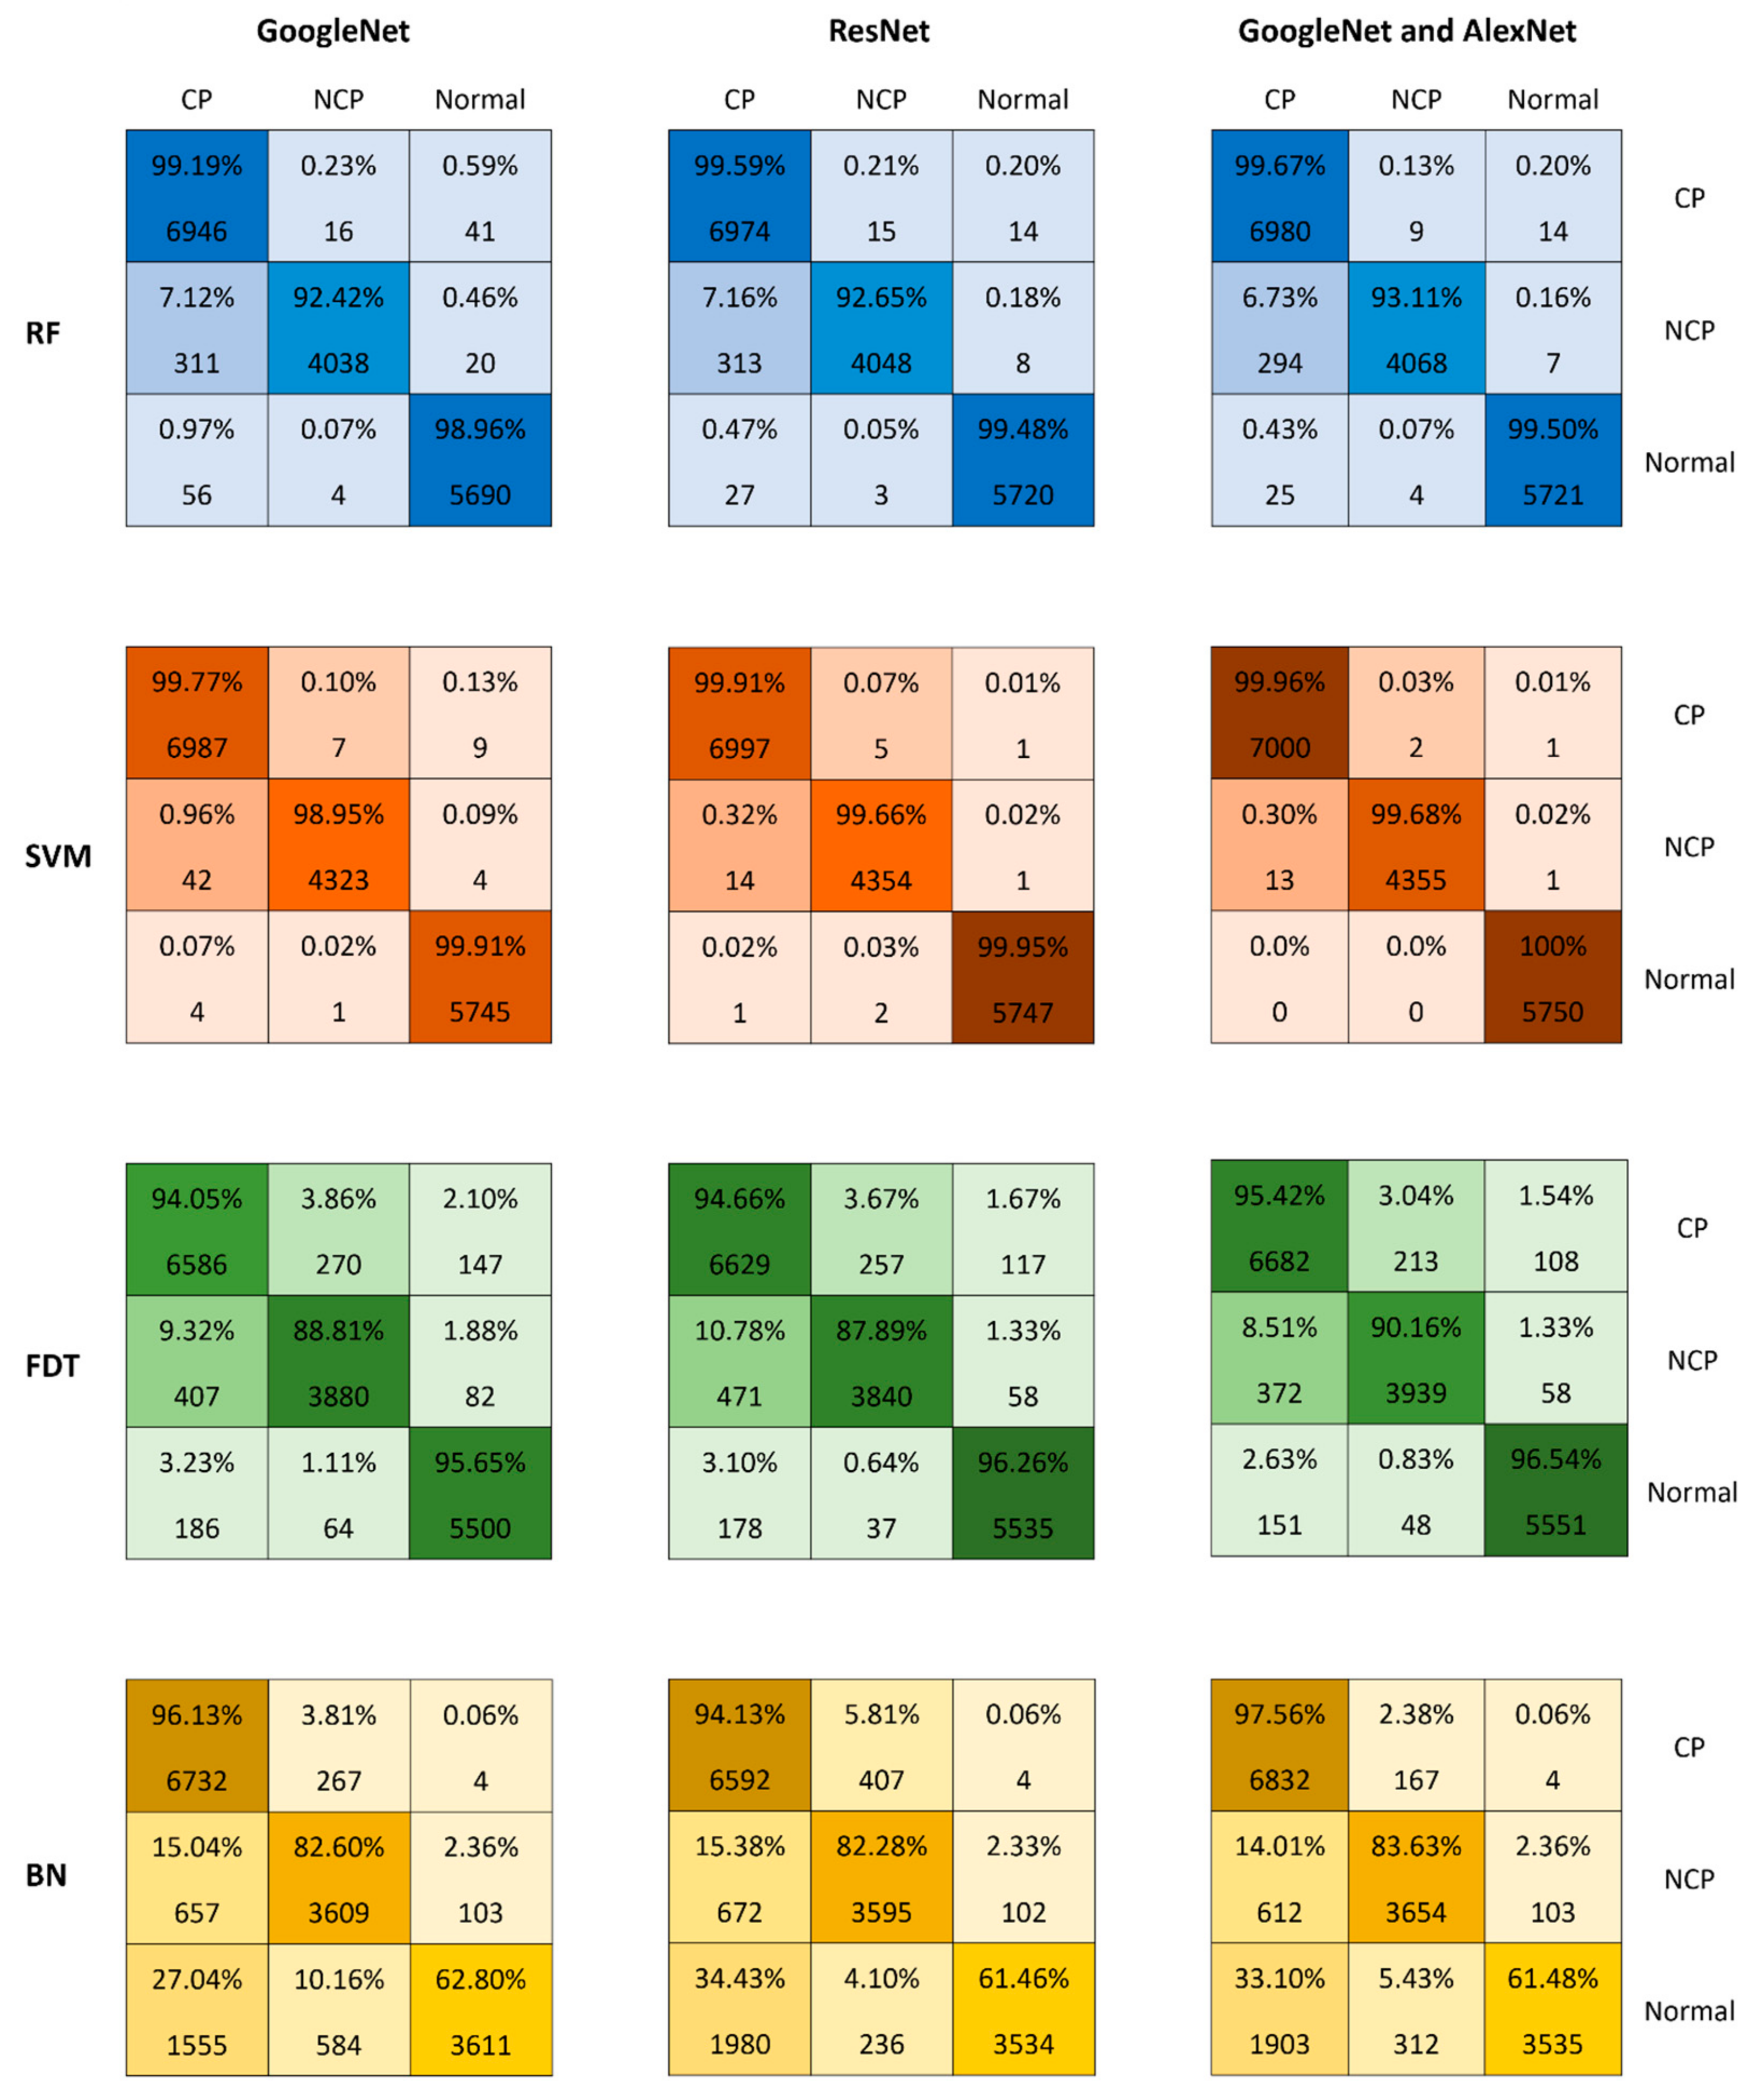

| Method | Accuracy | Precision | Recall | F1-Measure | Training Time |

|---|---|---|---|---|---|

| AlexNet | 98.49 | 0.986 | 0.977 | 0.982 | 25,568 |

| VGG16 | 97.32 | 0.971 | 0.960 | 0.972 | 73,756 |

| GoogleNet | 98.71 | 0.984 | 0.972 | 0.978 | 54,866 |

| Method | Accuracy | Precision | Recall | F1-Measure | Training Time |

|---|---|---|---|---|---|

| Random forest | 93.25 | 0.932 | 0.897 | 0.979 | 162 |

| Support vector machine | 99.61 | 0.996 | 0.994 | 0.997 | 6027 |

| Fast decision tree | 93.25 | 0.932 | 0.897 | 0.979 | 162 |

| Bayesian network | 81.49 | 0.81 | 0.729 | 0.937 | 178 |

| Method | Accuracy | Precision | Recall | F1-Measure | Training Time |

|---|---|---|---|---|---|

| Random forest | 97.78 | 0.978 | 0.967 | 0.999 | 202 |

| Support vector machine | 99.86 | 0.999 | 0.998 | 0.999 | 7513 |

| Fast decision tree | 93.47 | 0.999 | 0.998 | 0.999 | 133 |

| Bayesian network | 80.14 | 0.798 | 0.708 | 0.93 | 210 |

| Method | Accuracy | Precision | Recall | F1-Measure | Training Time |

|---|---|---|---|---|---|

| Random forest | 97.93 | 0.979 | 0.969 | 0.999 | 241 |

| Support vector machine | 99.90 | 0.999 | 0.998 | 0.999 | 12,382 |

| Fast decision tree | 94.45 | 0.944 | 0.915 | 0.984 | 302 |

| Bayesian network | 81.88 | 0.814 | 0.736 | 0.931 | 404 |

| Reference | Method | Data | Accuracy |

|---|---|---|---|

| Proposed method | Hybrid ResNet18 and GoogleNet 2000 features with SVM | CC-CCII dataset | 99.91% |

| Kang et al. (2020) [49] | A custom-designed 7-layered 3D CNN model | CC-CCII dataset | 88.94% |

| Xing et al. (2020) [50] | Hybrid active learning with 2D U-Net and residual network | CC-CCII dataset | 95% |

| Li et al. (2021) [51] | Hybrid generative adversarial network and DenseNet | CC-CCII dataset | 85% |

| Fu et al. (2021) [52] | Densely connected attention network (DenseNet) | CC-CCII dataset | 96.06% |